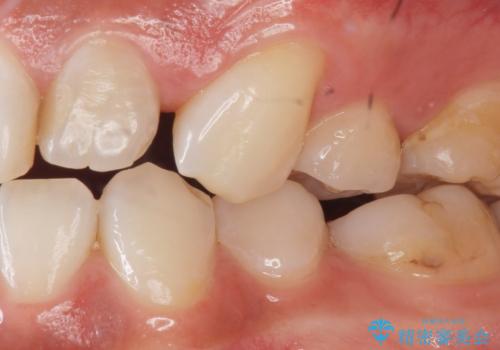

- 上の前歯の色と隙間を気にされ、来院された患者様です。

精査したところ、右上の側切歯(右上2)は神経が死んで変色しており、左上の側切歯と犬歯の間に2mm程度の隙間を認めました。

矯正せずに早く治したいという強いご希望により、セラミッククラウンによる補綴治療(上顎両側2の2本)を行いました。